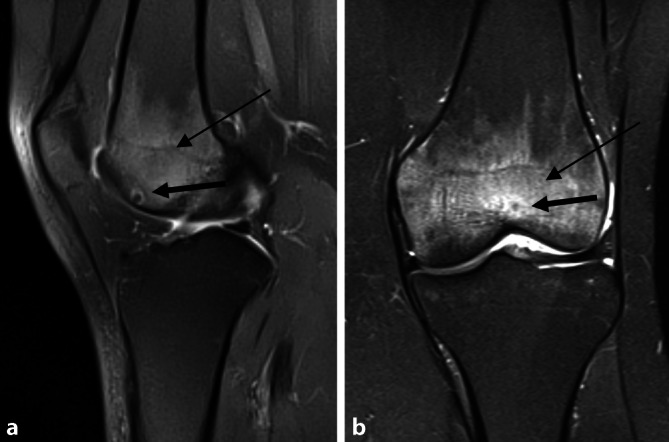

MRT des Kniegelenks zum Zeitpunkt der Operation sowie 3 Jahre zuvor. Zu allen Zeitpunkten zeigt sich ein hyperintenses Ödem in der T2-Wichtung im distalen Femur bei Nachweis eines Nidus in der Trochlea femoris (Abb. 1 und 3). Der Nidus ist in der T2-Wichtung charakterisiert durch eine Hyperintensität mit meist umgebener signalarmer Sklerosezone (Abb. 3). Im vorliegenden Fall weist der Nidus einen Bezug zur subchondralen Knochenlamelle und somit auch eine unmittelbare Nähe zum Gelenkknorpel auf (Abb. 3). Ein Gelenkerguss besteht nicht.

Bei progredienten MRT-Befunden und der Diagnosesicherung des Osteoidosteoms mittels CT (Abb. 2) wurde die Radiofrequenzablation mit den Kollegen der Radiologie ausführlich diskutiert. Diese war aber aufgrund der Nähe des Nidus zur subchondralen Lamelle und MRT-morphologisch vermutetem Kontakt zum Gelenkknorpel kontraindiziert (Abb. 5).